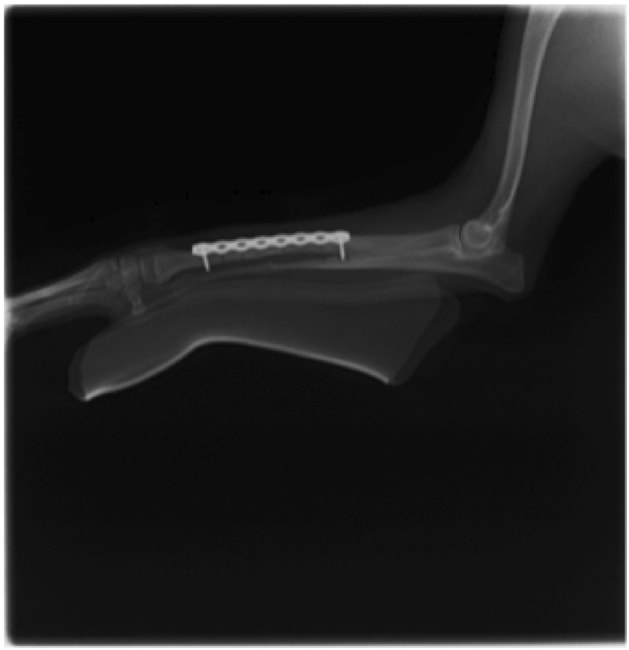

症例:交通事故による椎体脱臼

柴犬:9歳、避妊雌

交通事故直後、胸腰部に激しい疼痛、両後肢に完全麻痺を認め、シェフシェリントン徴候を呈していました。レントゲン検査において、第11-12胸椎間の脱臼が認められました。

脊髄の減圧、脊柱管の再構築・安定化を目的に、片側椎弓切除術およびMatrixMANDIBLE Plateによる椎体固定を実施しました。

隣接椎体を架橋するようにプレートを設置しました。

術後レントゲン写真